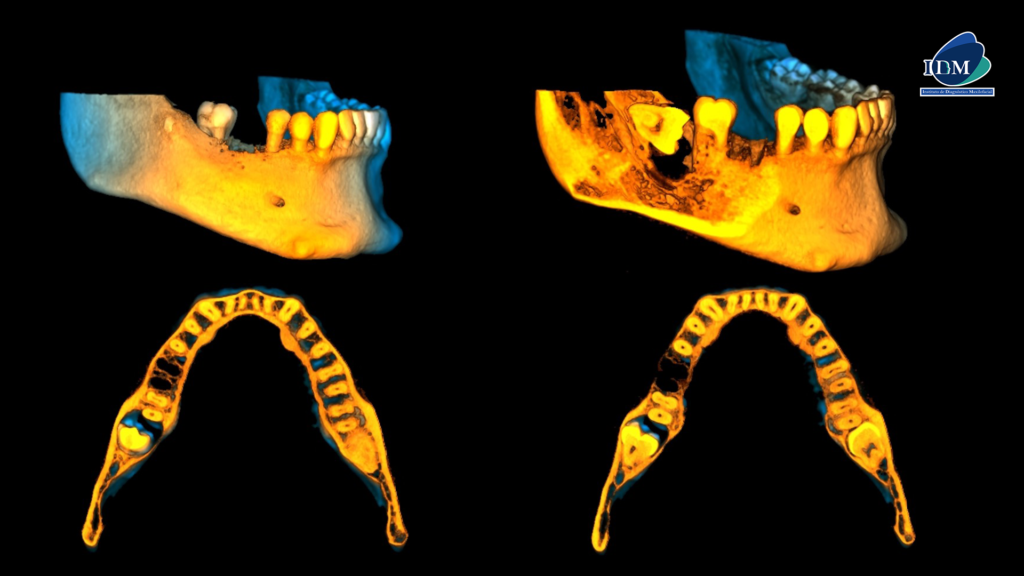

En las reconstrucciones 3D se representa de manera didáctica el compromiso que tiene la lesión con las estructuras adyacentes. (Figura 4).

RECONSTRUCCIÓN 3D

- Características imagenológicas sugerente de quiste dentigero.